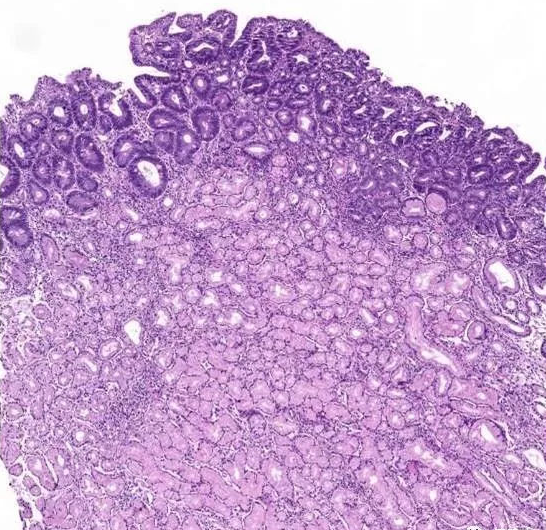

肠上皮化生是萎缩性胃炎的一种表现形式 。 很多人对肠上皮化生极为恐惧 , 以为出现肠上皮化生就离癌变不远了 。 这完全是一种错误的认识 。 萎缩性胃炎和肠上皮化生癌变率其实很低 。 只有伴有明显的异型增生(又称高级别上皮内瘤变) , 癌变率才会较高 , 需要及时治疗 。 即便是重度的萎缩或重度的肠上皮化生 , 只要没有明显的异型增生是不会癌变的 , 但容易引起消化不良症状 。

本文图片

萎缩性胃炎或肠上皮化生如果出现了异型增生就可能会发生癌变 , 因此出现这种情况 , 如果是轻度的异型增生(低级别的上皮内瘤变)可以每年做次内镜检查 , 监测复查便可;如果出现了重度的异型增生(高级别的上皮内瘤变) , 则需要住院治疗几天 , 尤其是用中医治疗 , 可使疾病愈合机率更大 。